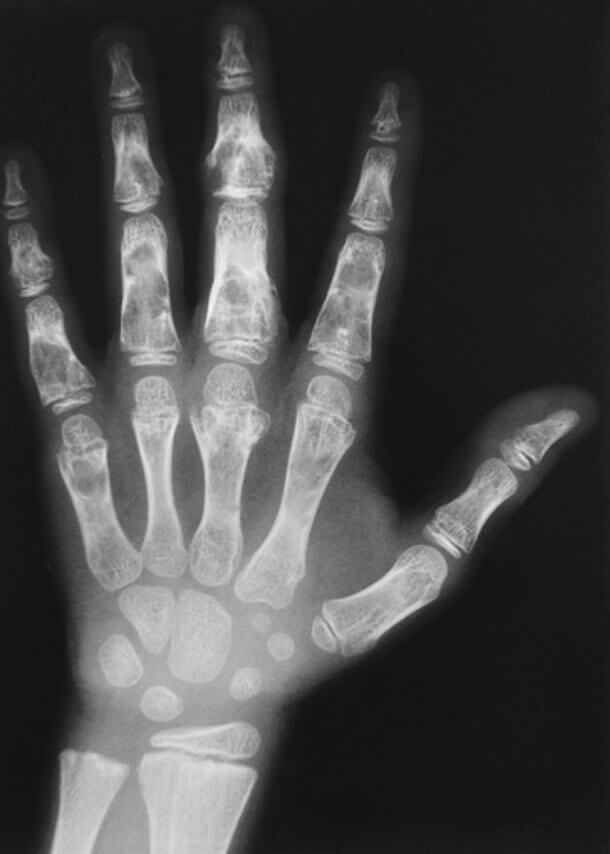

8

Q

Qual o diagnóstico?

A

Lesão lítica, com cortical insuflada e foco de calcificação interna

dx: Encondroma